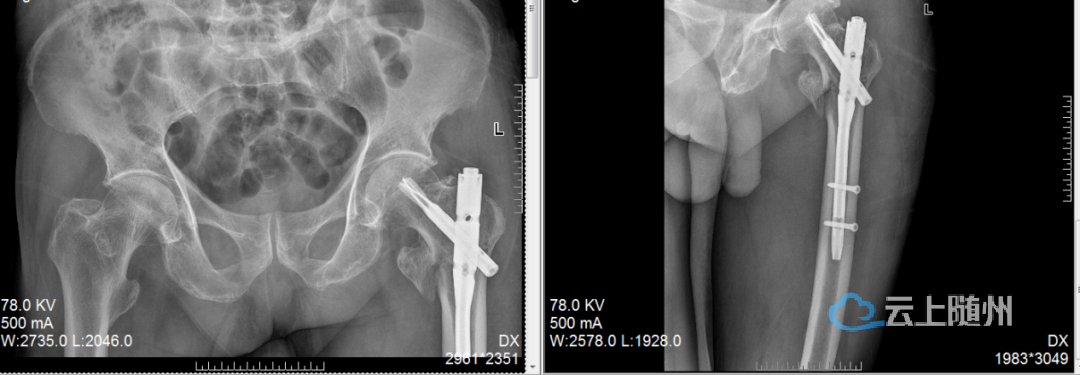

高龄老人髋部骨折,降低卧床风险

一位高龄老人摔伤导致髋部骨折,我们采用了微创的“钥匙孔”式微创内固定术。手术时间短、出血少,老人第二天就可以在床上坐起、活动腿脚,一周内尝试站立,大大降低了长期卧床的风险。